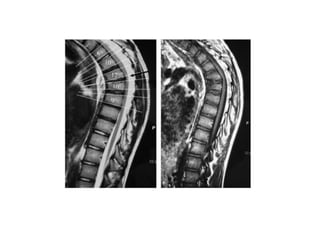

Diagnostic evaluation

• X-ray spine.

• PFT

• MRI

Diagnostic evaluation • X-rayspine. • PFT • MRI